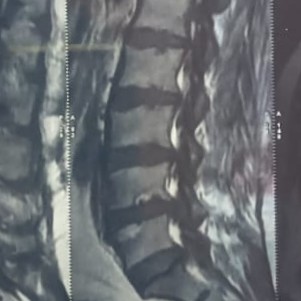

Why Choose an Endoscopic Spine Surgeon for Elderly Patients